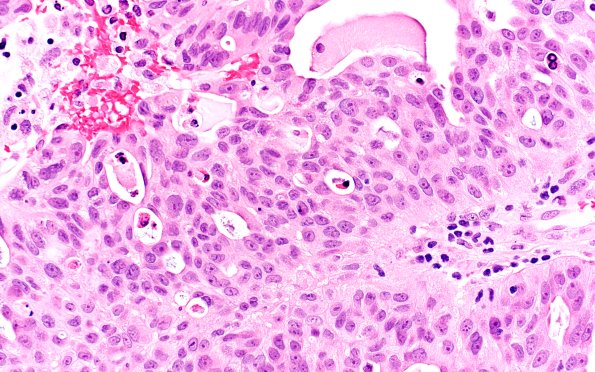

Washington University Experience | NEOPLASMS (METASTASES) | Microscopic | 96A2 Metastasis, Lung adeno (Case 96) H&E 40X

H&E-stained sections show a moderately differentiated metastatic adenocarcinoma with cribriform and glandular architecture.